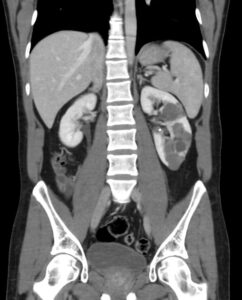

This 49 year old man had an abdominal CT as part of an emergency assessment for ?appendicitis.  No explanation for the pain was found, but he was noted to have multiple simple cortical cysts in his left kidney.  The visualised pancreas, aorta, right kidney, gall bladder and biliary tree all appeared normal and the spleen measured 9.8 cm, which was also normal.

Single image from CT with contrast